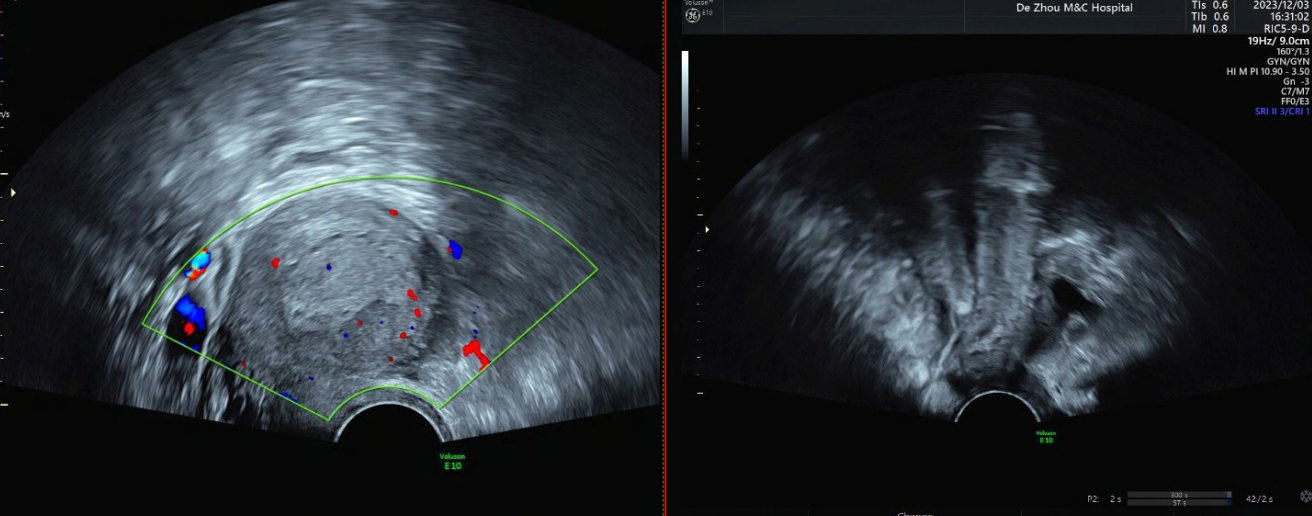

2023-12-03 B超:内膜厚度16mm,回声不均质,内见散在缝隙样无回声,CDFI:未见明显血流信号;左卵巢与子宫之间见17mmx10mm混合回声,内见5mmx3mm无回声,CDFI:周边半环状血流信号;

2023-12-03 急诊β人绒毛膜促性腺激素HCG:938.0 mIU/ml。